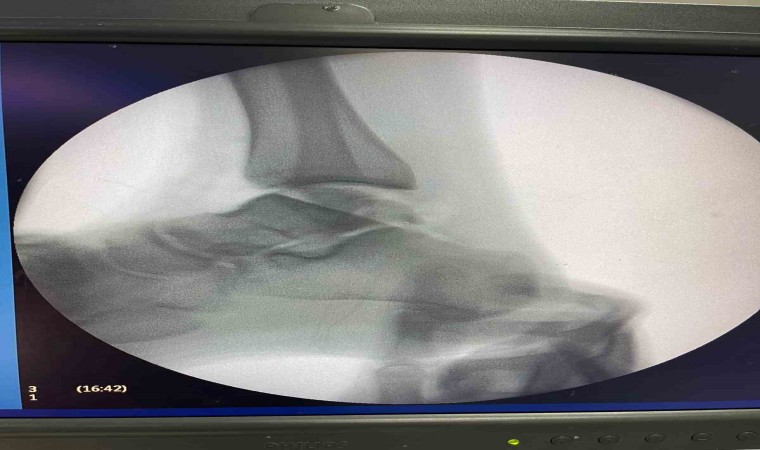

Sağlık alanındaki teknolojik gelişmelerin ve güncel uygulamaların yakından takip edildiği Balıkesir Üniversitesinde gerçekleştirilen ameliyatla ilgili bilgiler veren Ortopedi ve Travmatoloji Anabilim Dalı Öğretim Üyesi Doç. Dr. Aziz Atik; “Lenf kanseri olan 21 yaşındaki hastamız lenf kanseri tedavisi görerek sağlığına kavuşmuş ancak ilerleyen zamanlarda aldığı tedavilerin yan etkisi olarak ayak bileği kemiğinde çürüme meydana gelmiş. Bize başvuran hastamızın eklem yüzeyi bozulmuş ve hastamız yürümekte zorlanıyor, topallıyordu. Büyük bir lezyonu olan hastamıza büyük lezyonlarda uygulanan en iyi tedavi yöntemi olan ve nadir olarak yapılan bir ameliyatla kadavra donörden kemik ve kıkırdak doku nakli gerçekleştirdik.” ifadelini kullandı. Ülkemizde kemik ve kıkırdak bankası olmadığının altını çizen Doç. Dr. Aziz Atik, yurt dışından bir donör bulmak için çalışmalar yaptıklarını ve yurtdışından kemik bulunduğunda ivedi bir şekilde ameliyatı gerçekleştirdiklerini söyledi. Ameliyatın son derece başarılı geçtiğini belirten Doç. Dr. Aziz Atik, güzel bir eklem düzeyi elde ettiklerini ve ameliyatla genç bir insanın topallamadan, ağrısız yürümesini hedeflendiklerini dile getirdi.